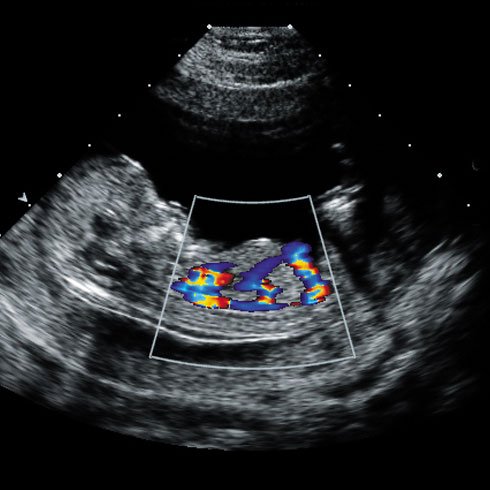

Colour Doppler